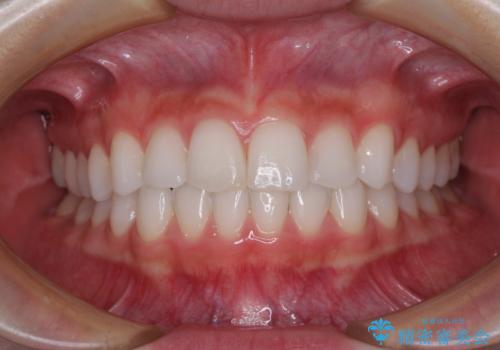

セラミッククラウンを装着する前に仮歯を装着しましたが、その時点で強い痛みはほぼ改善され、セラミッククラウン装着後には痛みはもちろん、しみる症状も感じることがなくなりました。